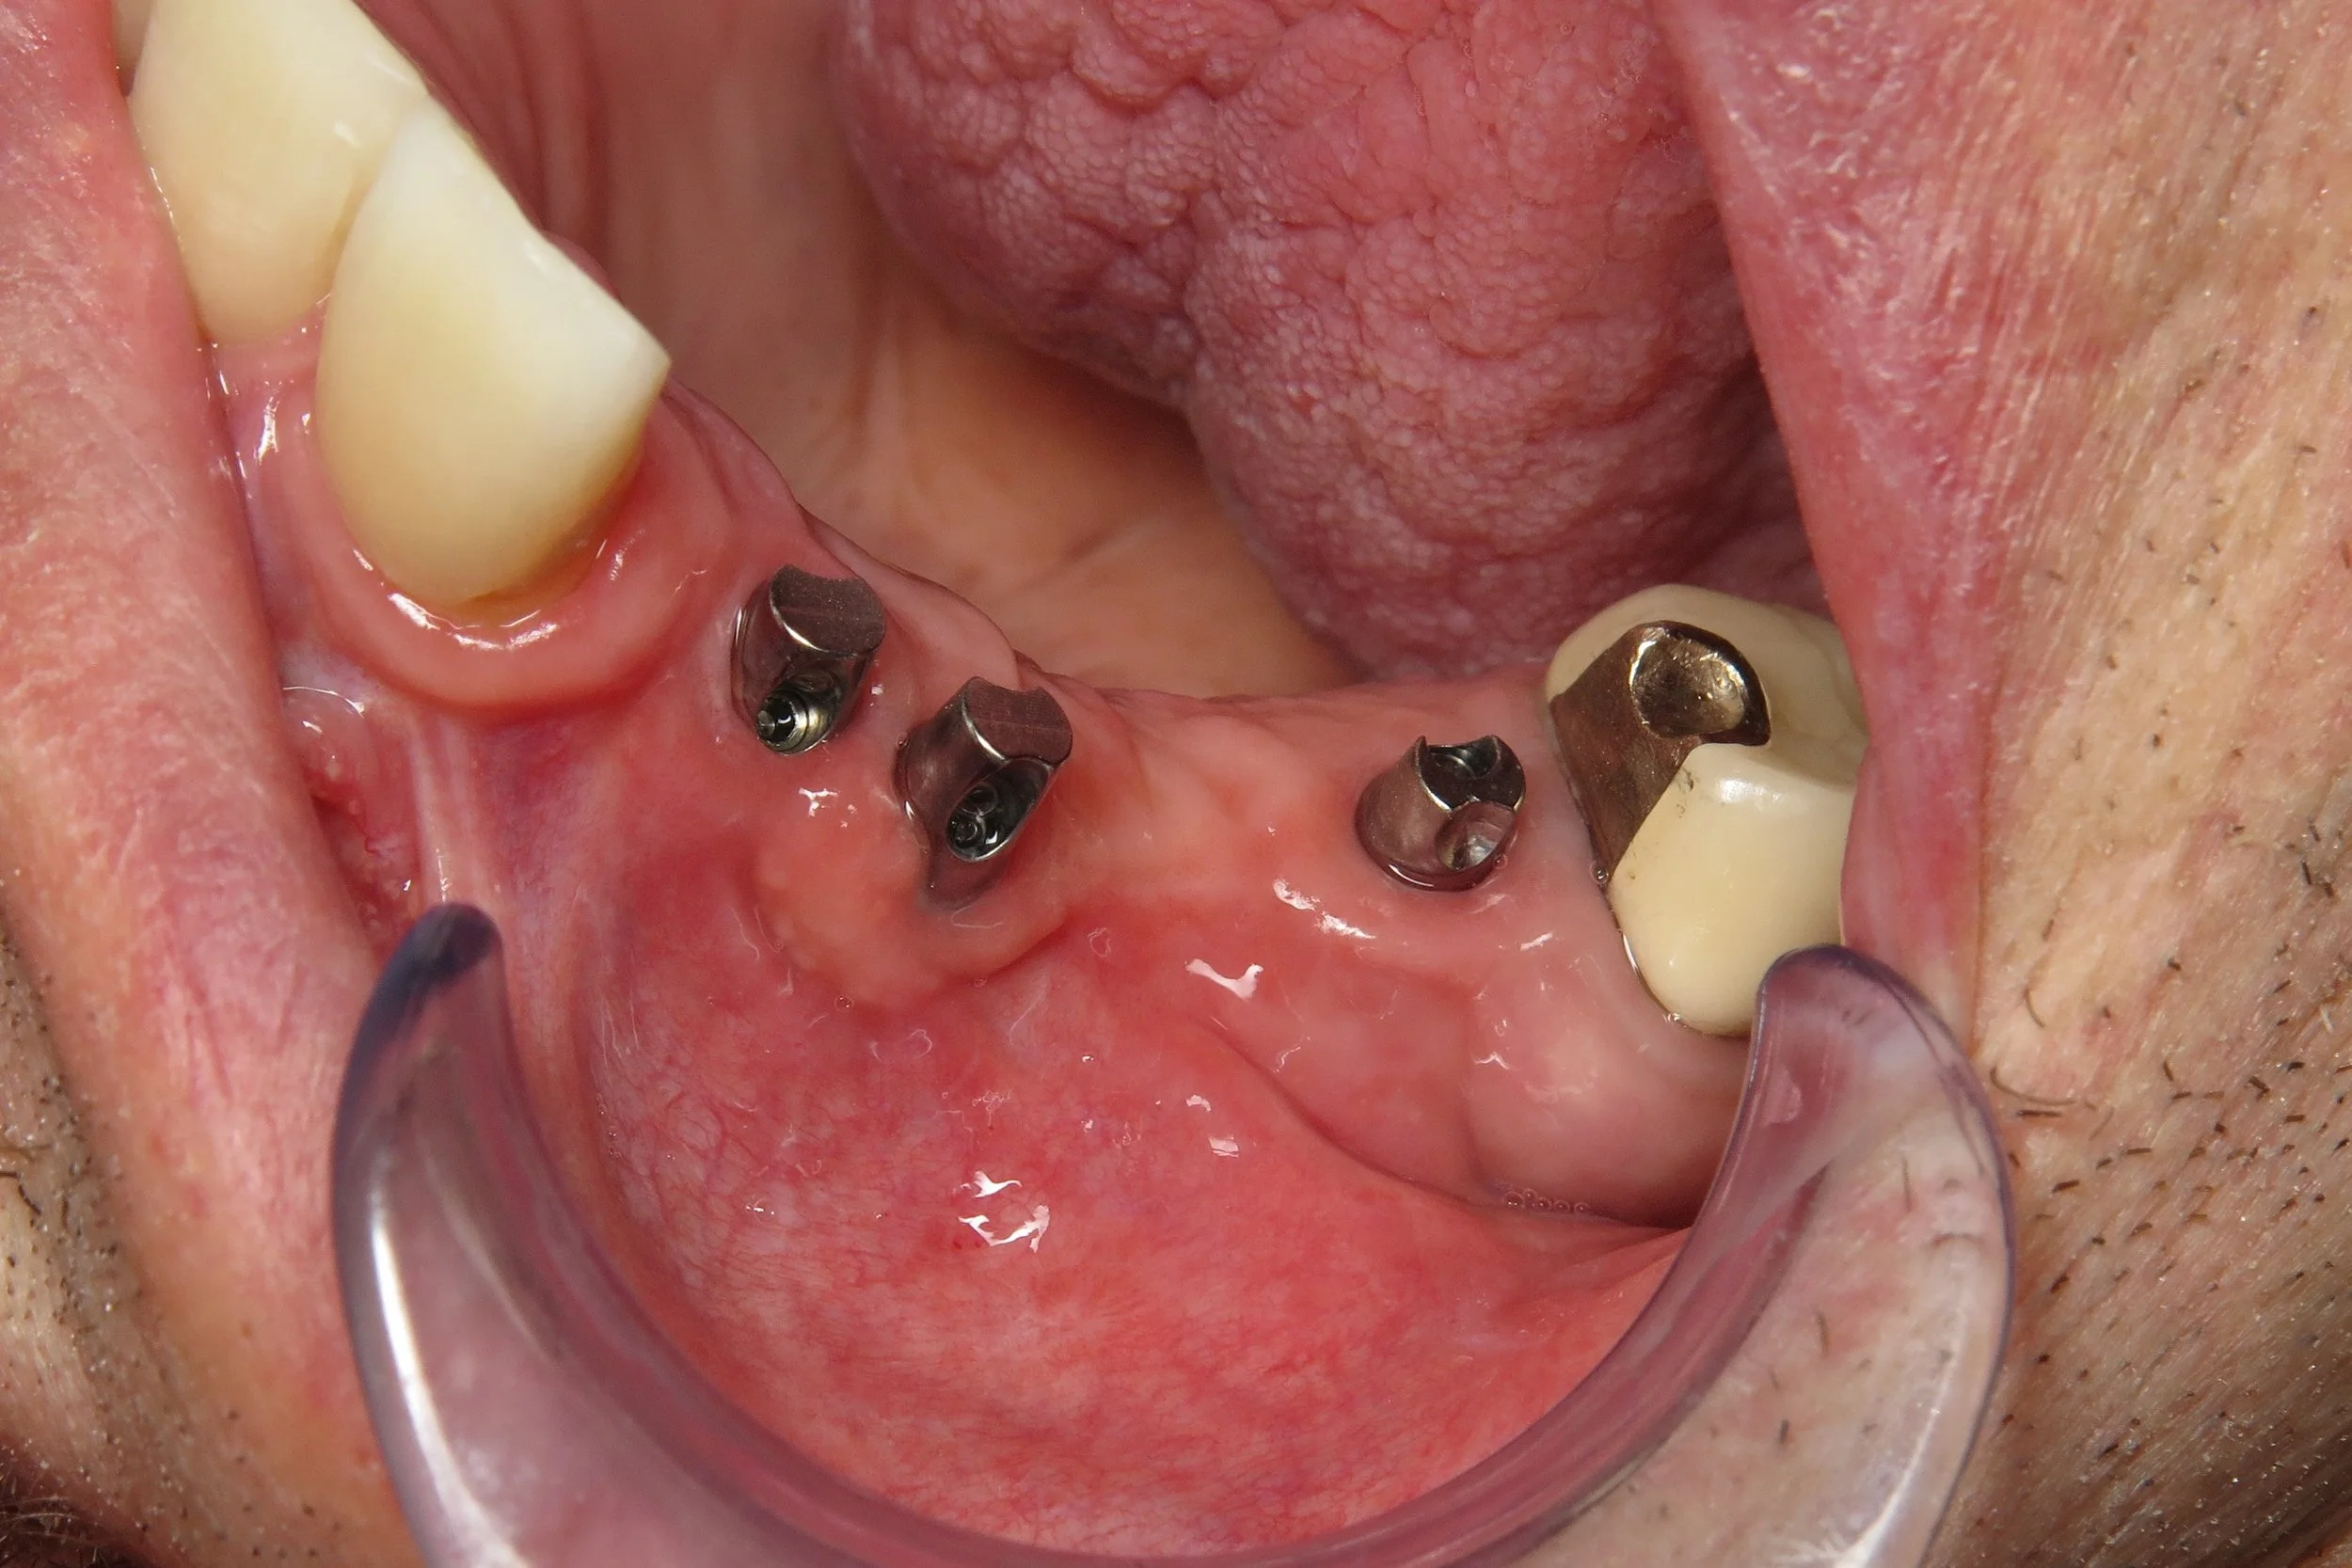

1. Implant Body (Root / Surgical Post)

2. Abutment

3. Gold Retentive Cap

The following cases were done by Dr. Johansen: